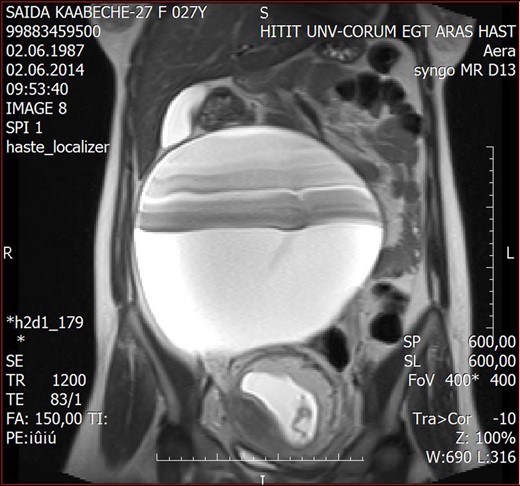

A 27-year-old female presented to the Hitit University Training Hospital for her routine pregnancy checkup. She was asymptomatic and was 17 weeks pregnant according to her last menstrual period. Her medical, surgical, and obstetric background was unremarkable, and she had considered her pregnancy up to this day unexceptional. On abdominal examination, a smooth painless mass arising from the right hemi-pelvis, extended up to a level just 10 cm above the umbilicus. An ultrasound scan confirmed the presence of a live 17-week gestation accompanied by an incidental cystic mass measuring ∼210 × 180 × 120 mm. Blood samples for serum tumor markers were drawn and the results were within normal limits (Ca-125: 8.6 U/ml, alpha-fetoprotein: 25.4 ng/ml). Magnetic resonance imaging (MRI) reported a 203 × 210 mm cystic mass, while all other pelvic structures were denoted as being within normal limits (Fig. 1).